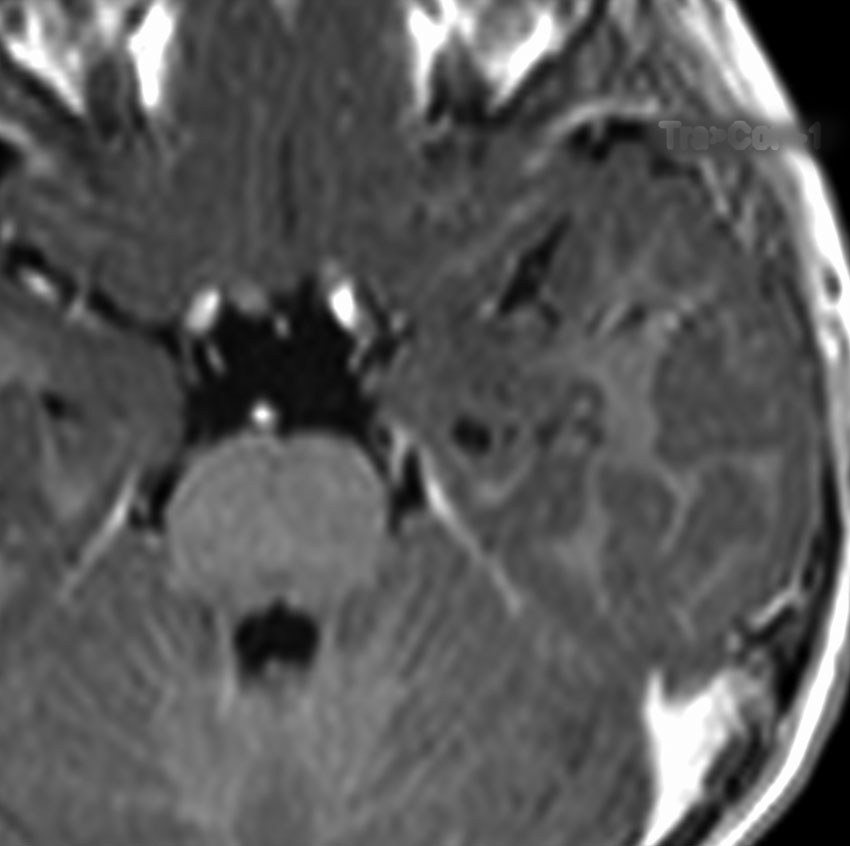

第4室床過誤腫の典型例です

新生児期より動作停止と右眼瞼のちく搦,4ヶ月で右眼の閉眼と口角の引きつれ(顔面けいれん)が目立つようになりました。2歳時には数十秒ごとに発作を繰り返していました。

MRIでは橋の背側(第4脳室床)にT1/T2で等信号の隆起(腫瘤)がみられました。